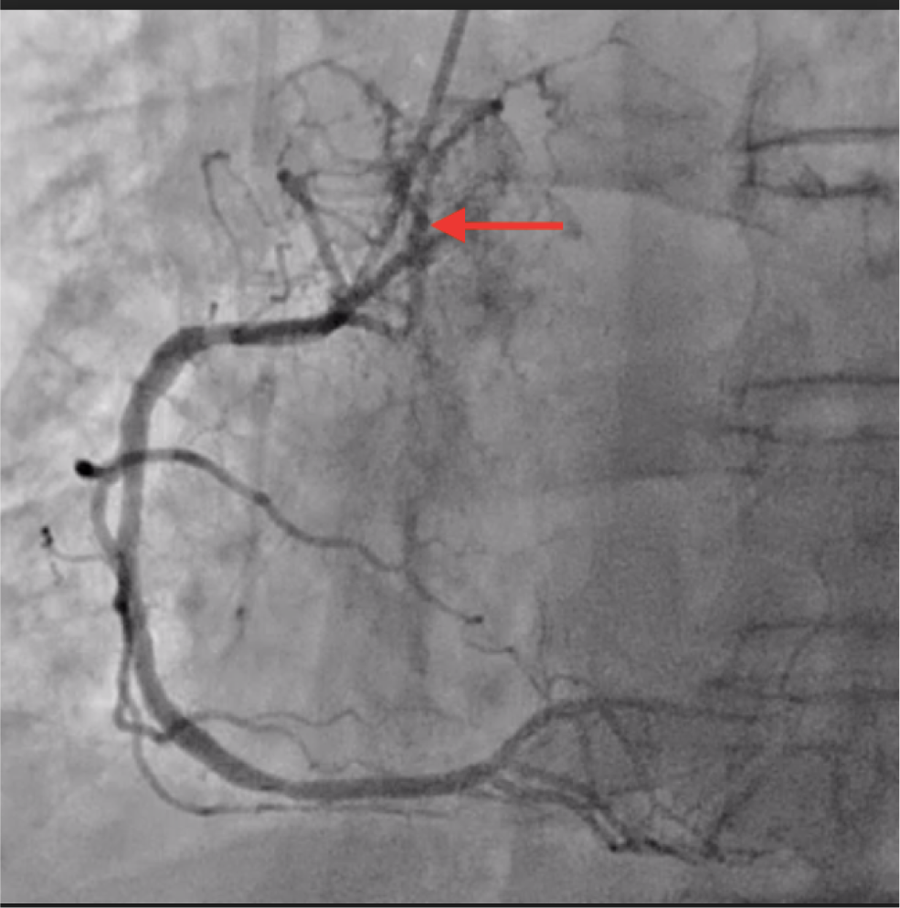

Coronary angiography highlighted a right dominance, tandem significant stenosis first segment of left anterior descending artery with ostial significant stenosis diagonal of small caliber with kinetics appearing altered in territory first segment of left anterior descending artery. Significant stenosis bisecting with a poorly developed downstream bed. An atypical coronary fistula was noted, arising from a branch of right coronary artery and perfusing the bronchial tumor (coronaro-bronchial fistula) (Figure 1).

Figure 1

Fistula origin (coronary angiography).